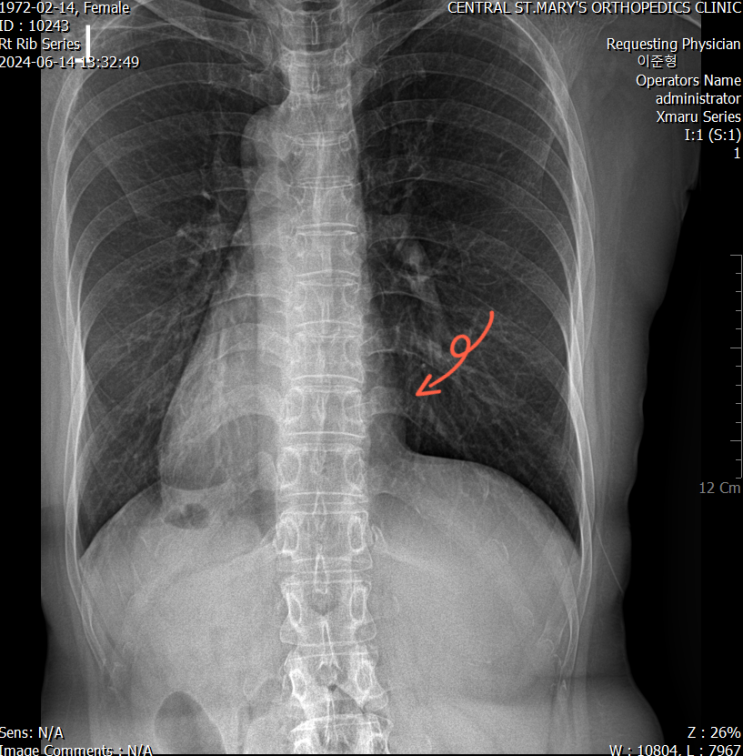

x-rayㅣ Lower rib 이 떠있다?

x-rayㅣ오십견과 Rib Fascia

51세 여성. 주 증상 : Rt frozen shoulder. x-ray 만 보더라도 흉곽의 긴장이 심하신 상태, 우측 요방형근...